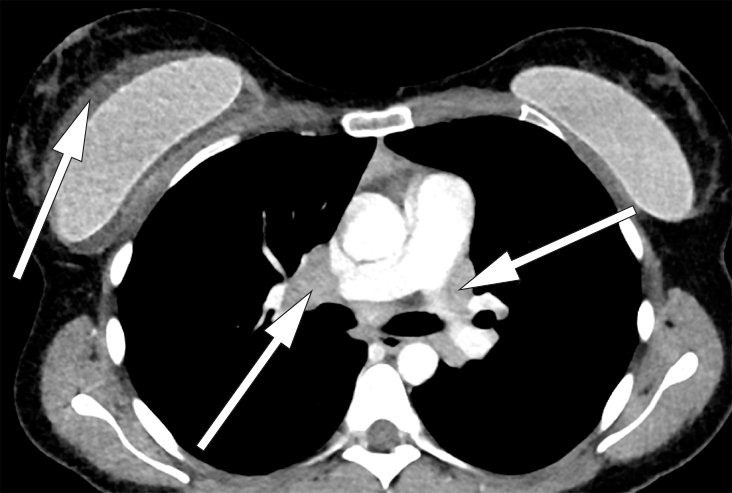

På bakgrunn av pasientens symptomer med nattesvette og ømhet i aksille ble det rekvirert CT collum og thorax.

CT thorax viste forstørrede lymfeknuter i mediastinum og lungehili (fig 1). Angiotensinkonverterende enzym (ACE) var lett forhøyet, til 85 U/l (< 60 U/l).